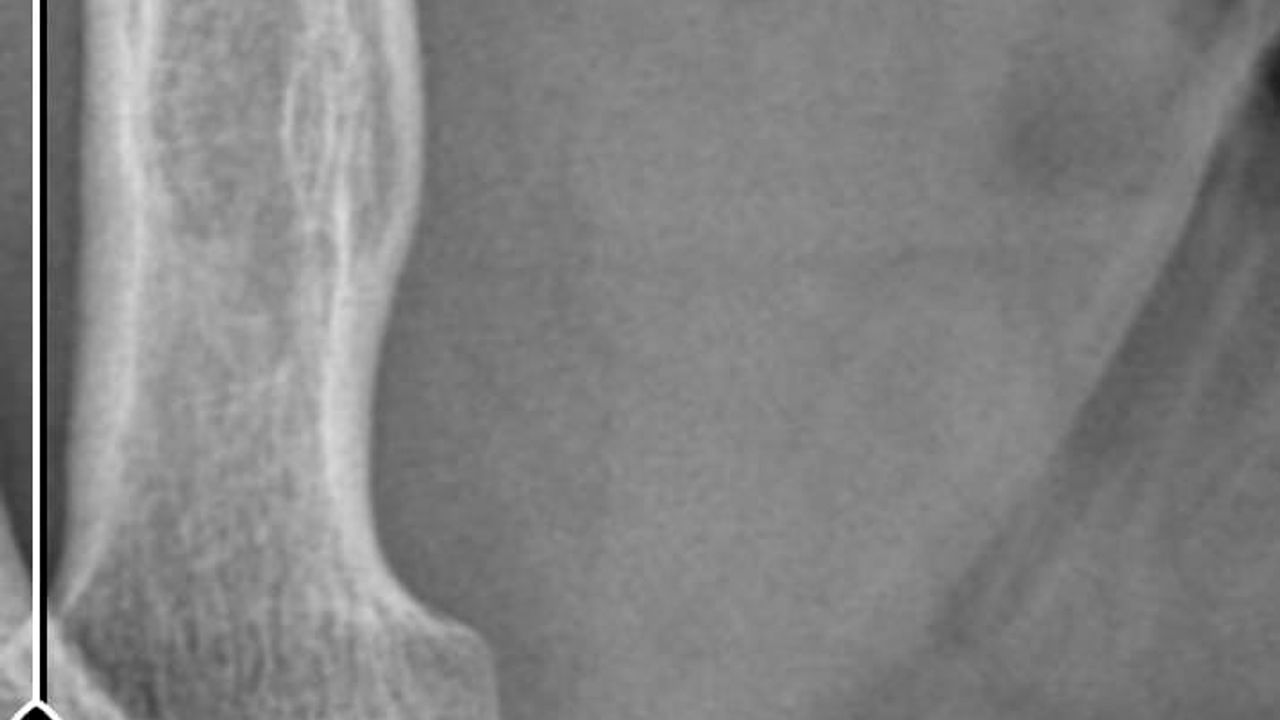

Ameliyatların ardından kolunda ağrılar hissettiğini söyleyen Güleryüz, kolunda metal parça bulunduğunu ve bu parçanın parmak bölgesinden dirseğe doğru ilerlediği iddiasını dile getirdi. Ayrıca çalıştığı fabrikada temizlik personeli olan Güleryüz'ün tedavi sürecinde işten çıkarıldığı öğrenildi.